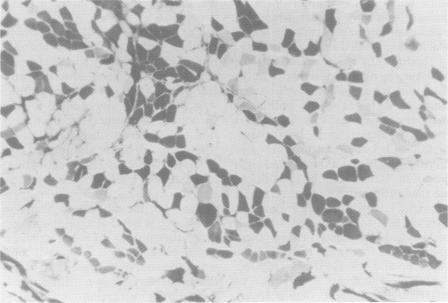

本项目的目的是通过将横断的神经末端植入麻痹的肌肉,尝试恢复近期经实验去神经支配的左侧环杓后肌的外展功能。在6匹小马中,将第二颈神经的切断端植入左侧环杓后肌上所做的一个切口内。用一根5-0聚丙烯缝线将神经外膜与肌外膜相连,把神经末端固定到位。在此手术过程中,左侧喉返神经被横断。所有6匹小马在手术后立即出现完全性左侧喉偏瘫的体征。术后,每月对所有小马进行定性主观检查,通过内镜检查杓状软骨外展的证据,同时通过测量声门裂左右半侧的横截面积进行定量评估。术后6个月,6匹小马中有4匹在内镜检查中出现了部分外展的主观证据。声门裂横截面积的测量显示,术后立即总面积减少了38%。从术后立即评估到术后6个月评估,声门裂的横截面积没有显著变化。大体尸检显示,左侧环杓后肌部分萎缩,与右侧环杓后肌相比,肌肉质量减少了24%-55%。组织病理学研究显示存在大肌纤维簇的区域。(摘要截选至250字)